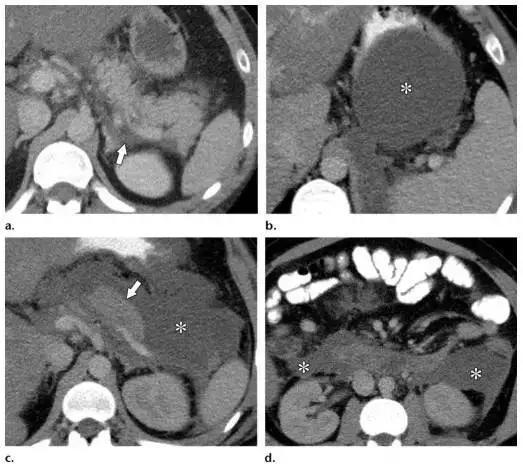

APFCs 发生于发病 4 周内,仅见于 IEP 患者。因为没有坏死物,APFCs 表现为胰周无壁均质液性密度(图 4)。

APFCs 仅见于胰周,如果胰腺实质内有相似表现的病灶为 ANC,诊断就不再是 IEP 而是坏死性胰腺炎。多数 APFCs 能够自发吸收,而且引流有继发感染的可能,所以不建议引流治疗。

患病早期有些病例 IEP 和坏死性胰腺炎在增强 CT 上难以鉴别,相应 APFC 和 ANC 也鉴别困难。通常,在患病第 2 周增强 CT 检查可以更好的显示 ANC 内部不均质的表现。

图 4 合并 APFCs 的 49 岁男性 IEP 患者。a 腹痛第一天,可见肾脏左前方少量均质液性密度(箭头)。胰腺强化正常。b~d 腹痛发生后 10 天,小网膜囊(b)、胰周(c)、双侧肾前间隙(d)可见大量均质液性密度,征象和 APFCs 相符。图 c 中的箭头指正常强化的胰尾